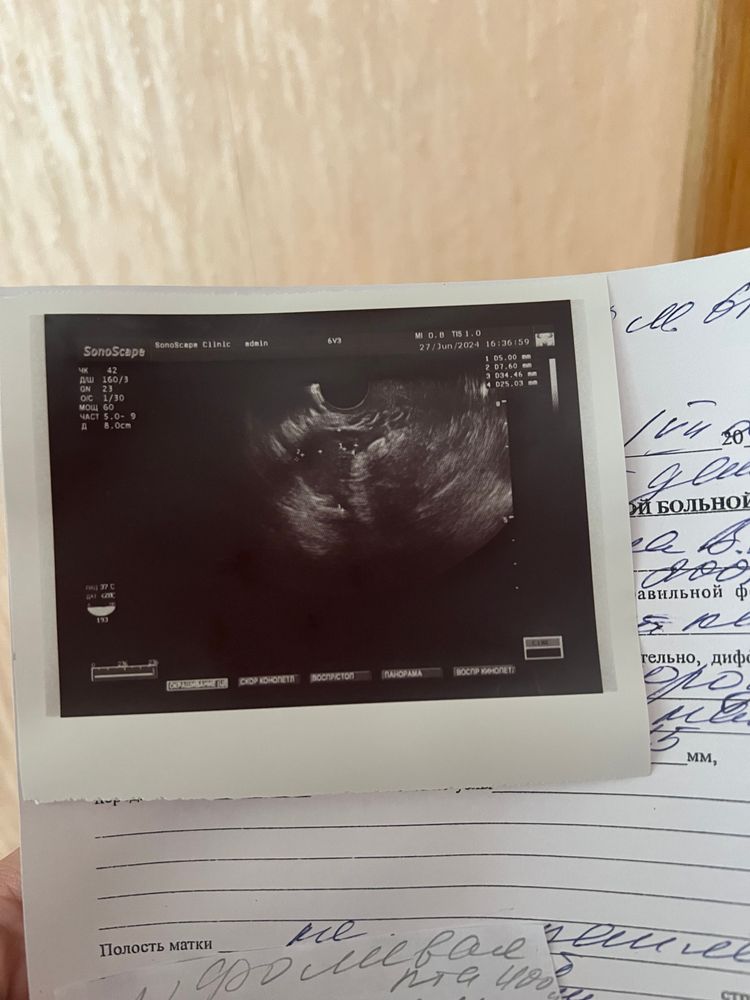

Lera в Зачатие год Фолликулы не всегда же маленькие могут быть? УЗИ Сходила к гинекологу,сегодня 22 день цикла посмотрела сказала овульки не было,фолликулы маленькие завтра иду сдавать дефициты ,и поправлять надеюсь скоро будут посты о беременности 🩷 Посмотрите еще 20 записей на эту тему Отменить Ответить 10дц(при цикле 32дня) эндометрий 5,7мм по результату узи Чаты Беременных Выберите чат: Январята-2026 Февралята-2026 Мартята-2026 Апрелята-2026 Майчата-2026 Июнята-2026 Июлята-2026 Августята-2026